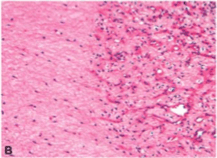

Dr. Amy Storfa: Hematoxylin and eosin-stained sections of the core biopsy showed a tumor composed of relatively small, uniform spindle cells with eosinophilic cytoplasm and bland nuclei with no appreciable cytologic atypia. The background showed various numbers of medium- to large-sized blood vessels, some with focally hyalinized walls (Figure 1A, 1B). Mitotic figures were not identified. Immunohistochemical stains for smooth muscle actin, desmin, vimentin, estrogen receptor, and progesterone receptors were positive; an immunohistochemical stain for S-100 was negative. The diagnosis was aggressive angiomyxoma, also known as deep angiomyxoma.

(A) Hematoxylin and eosin (H&E) stain of aggressive angiomyxoma showing ahypocellular tumor with numerous variable-sized blood vessels (magnification X100);

(B) H&E stain of aggressive angiomyxoma displaying proliferating capillary-sized blood vessels on the right and hypocellular stroma with spindle-shaped cells showing minimal cytologicatypia on the left (magnification X200);